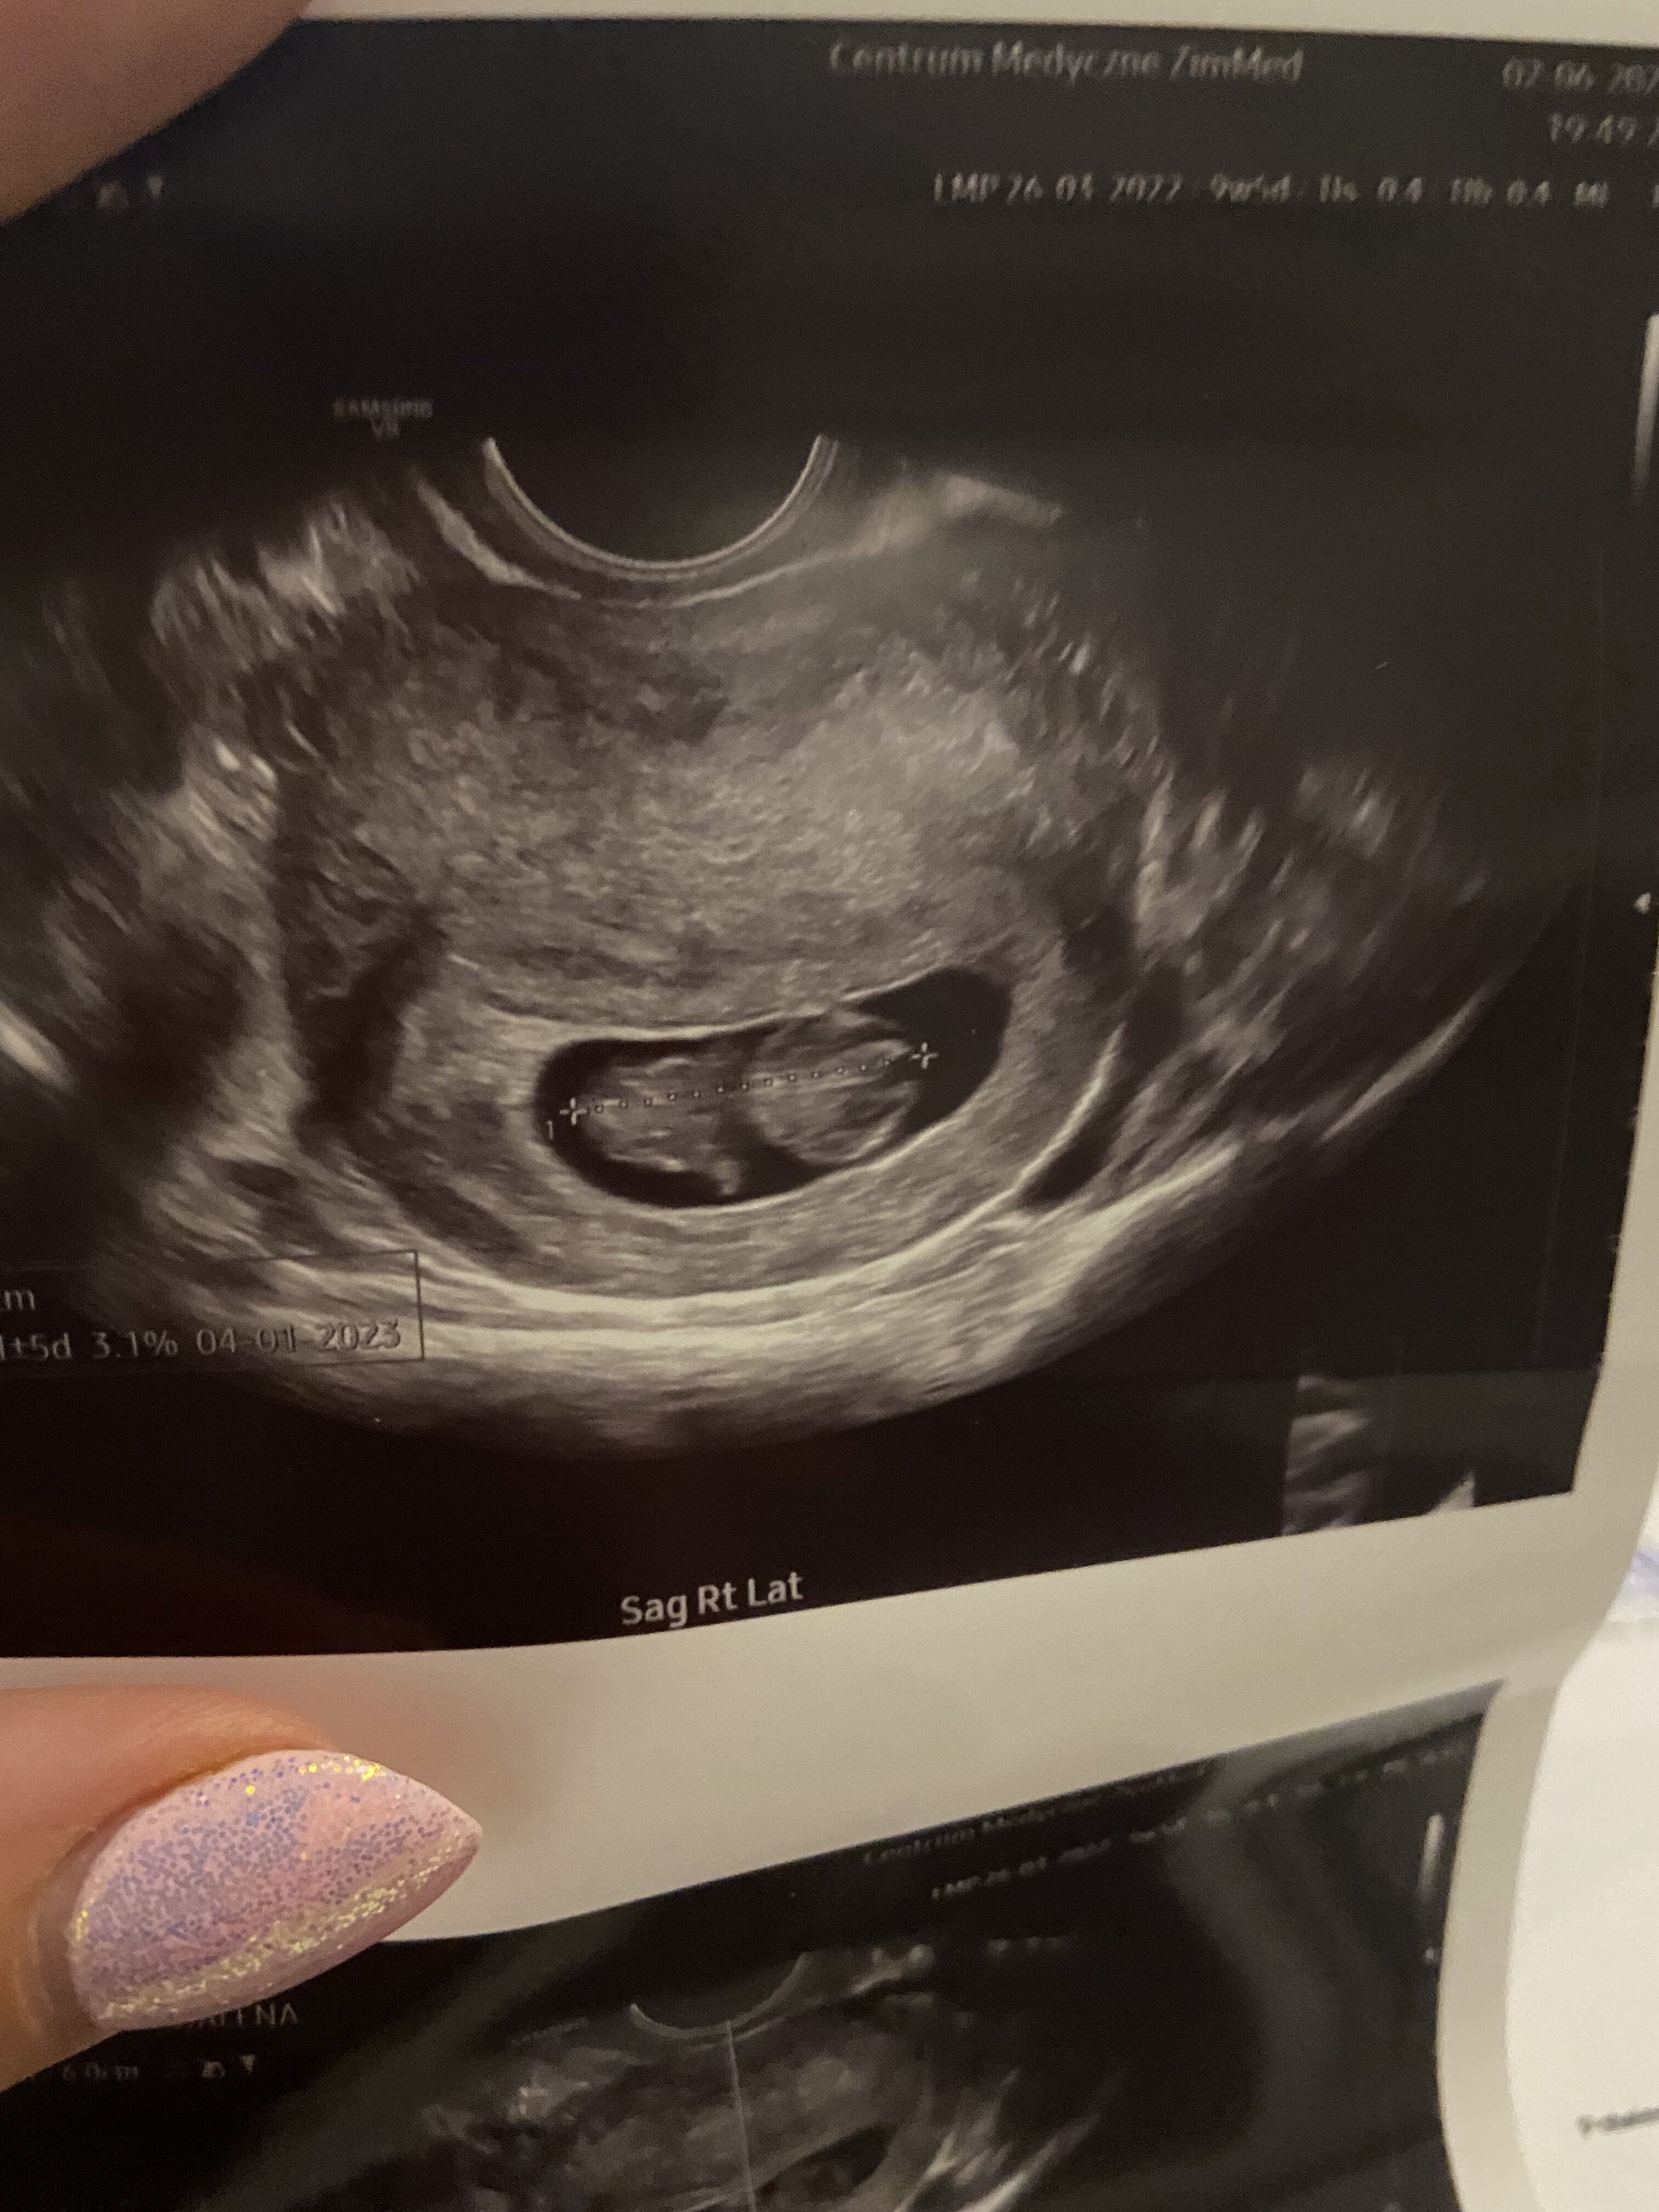

Nie mam jakichś szczególnych objawów, co dodatkowo mnie stresowało, zero mdłości, ból piersi delikatny od samego początku ciąży, jedynie co, to duża senność i zmęczenie. Wczoraj piersi przestały bolec mnie całkowicie, są jedynie powiększone. Oczywiście ustanie tego i tak minimalnego bólu bardzo mnie wystraszyło, przepłakałam cały dzień, po czym umowilam się na prywatna wizytę. Szlam na nią ze łzami w oczach, przekonana o tym, że usłyszę, że to już koniec naszej ciążowej przygody. Co zobaczyłam? 2,4 cm człowieczka, FHR 174, machającego nóżkami i rączkami

pęcherzyk ciążowy również przestał być zmartwieniem, wyglada nareszcie normalnie. Dzisiaj 9+3

Mam nadzieję, że limit nieszczęść został już wyczerpany, za 3 tygodnie prenatalne. Dodaję zdjęcie naszego największego skarbu z wielką nadzieją, że na przełomie roku weźmiemy go w swoje ramiona